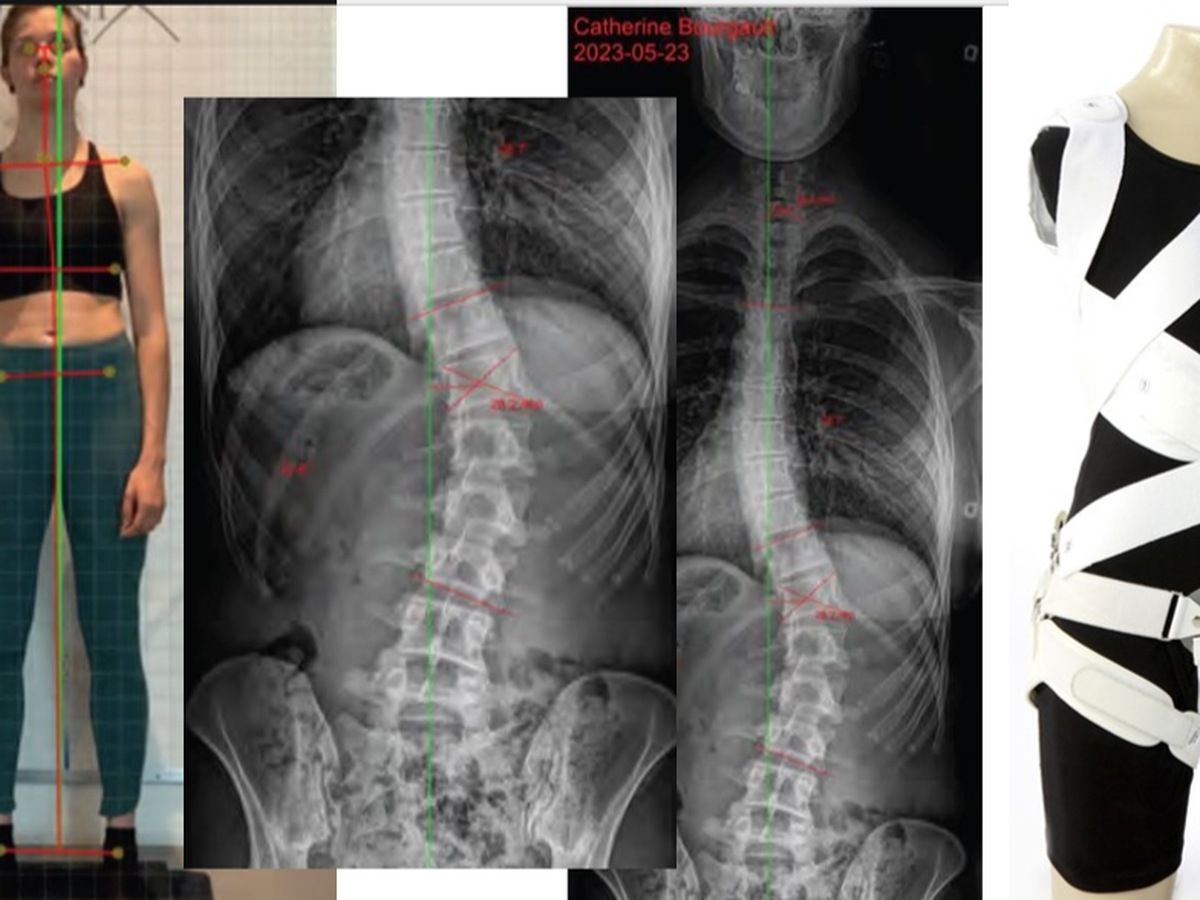

La source du problème, une scoliose idiopathique de 43 degrés (déformation tridimensionnelle de la colonne vertébrale). À 20 ans, on me parlait d'invalidité, j'ai pris du recul et fait beaucoup de travail psychologique (et d'aquaforme hihi) afin de me permettre de reprendre le sport, mais surtout de retrouver un certain confort au quotidien. Or, la dernière année a été particulière ardue, mes douleurs se sont propagées pour la première fois dans toute ma jambe droite, affectant l'usage de celle-ci et m'obligeant à arrêter tout effort physique (douleurs neurologiques causées par ma scoliose qui provoque un effondrement de disque vertébral). Je ne réussis toujours pas après 9 mois de traitement à retrouver un niveau de contrôle sur ma douleur dont j'avais acquis dans les dernières années, niveau qui me permettait de faire du sport et mes tâches quotidiennes.

Après plusieurs semaines de réflexion, j'ai décidé de consulter une spécialiste en scoliose qui me recommande l'achat d'un corset dynamique de correction pour limiter les impacts de mes déviations (sténose et arthrose principalement). Or, le corset à lui seul se vend 4750$ (non couvert), en plus d'un protocole de soins pour les prochains mois qui me coûtera près de 5 000$ (j'ai déjà atteint le montant de 900$ en 1 mois en consultations/ajustements avec la spécialiste, pour vous donner une petite idée). Vous comprendrez que le 300$ couvert par mes assurances par année avait déjà été largement dépassé, avant même d'être référée à cette spécialiste, car depuis janvier 2023 seulement, mes frais de santé ont atteint 2155$.